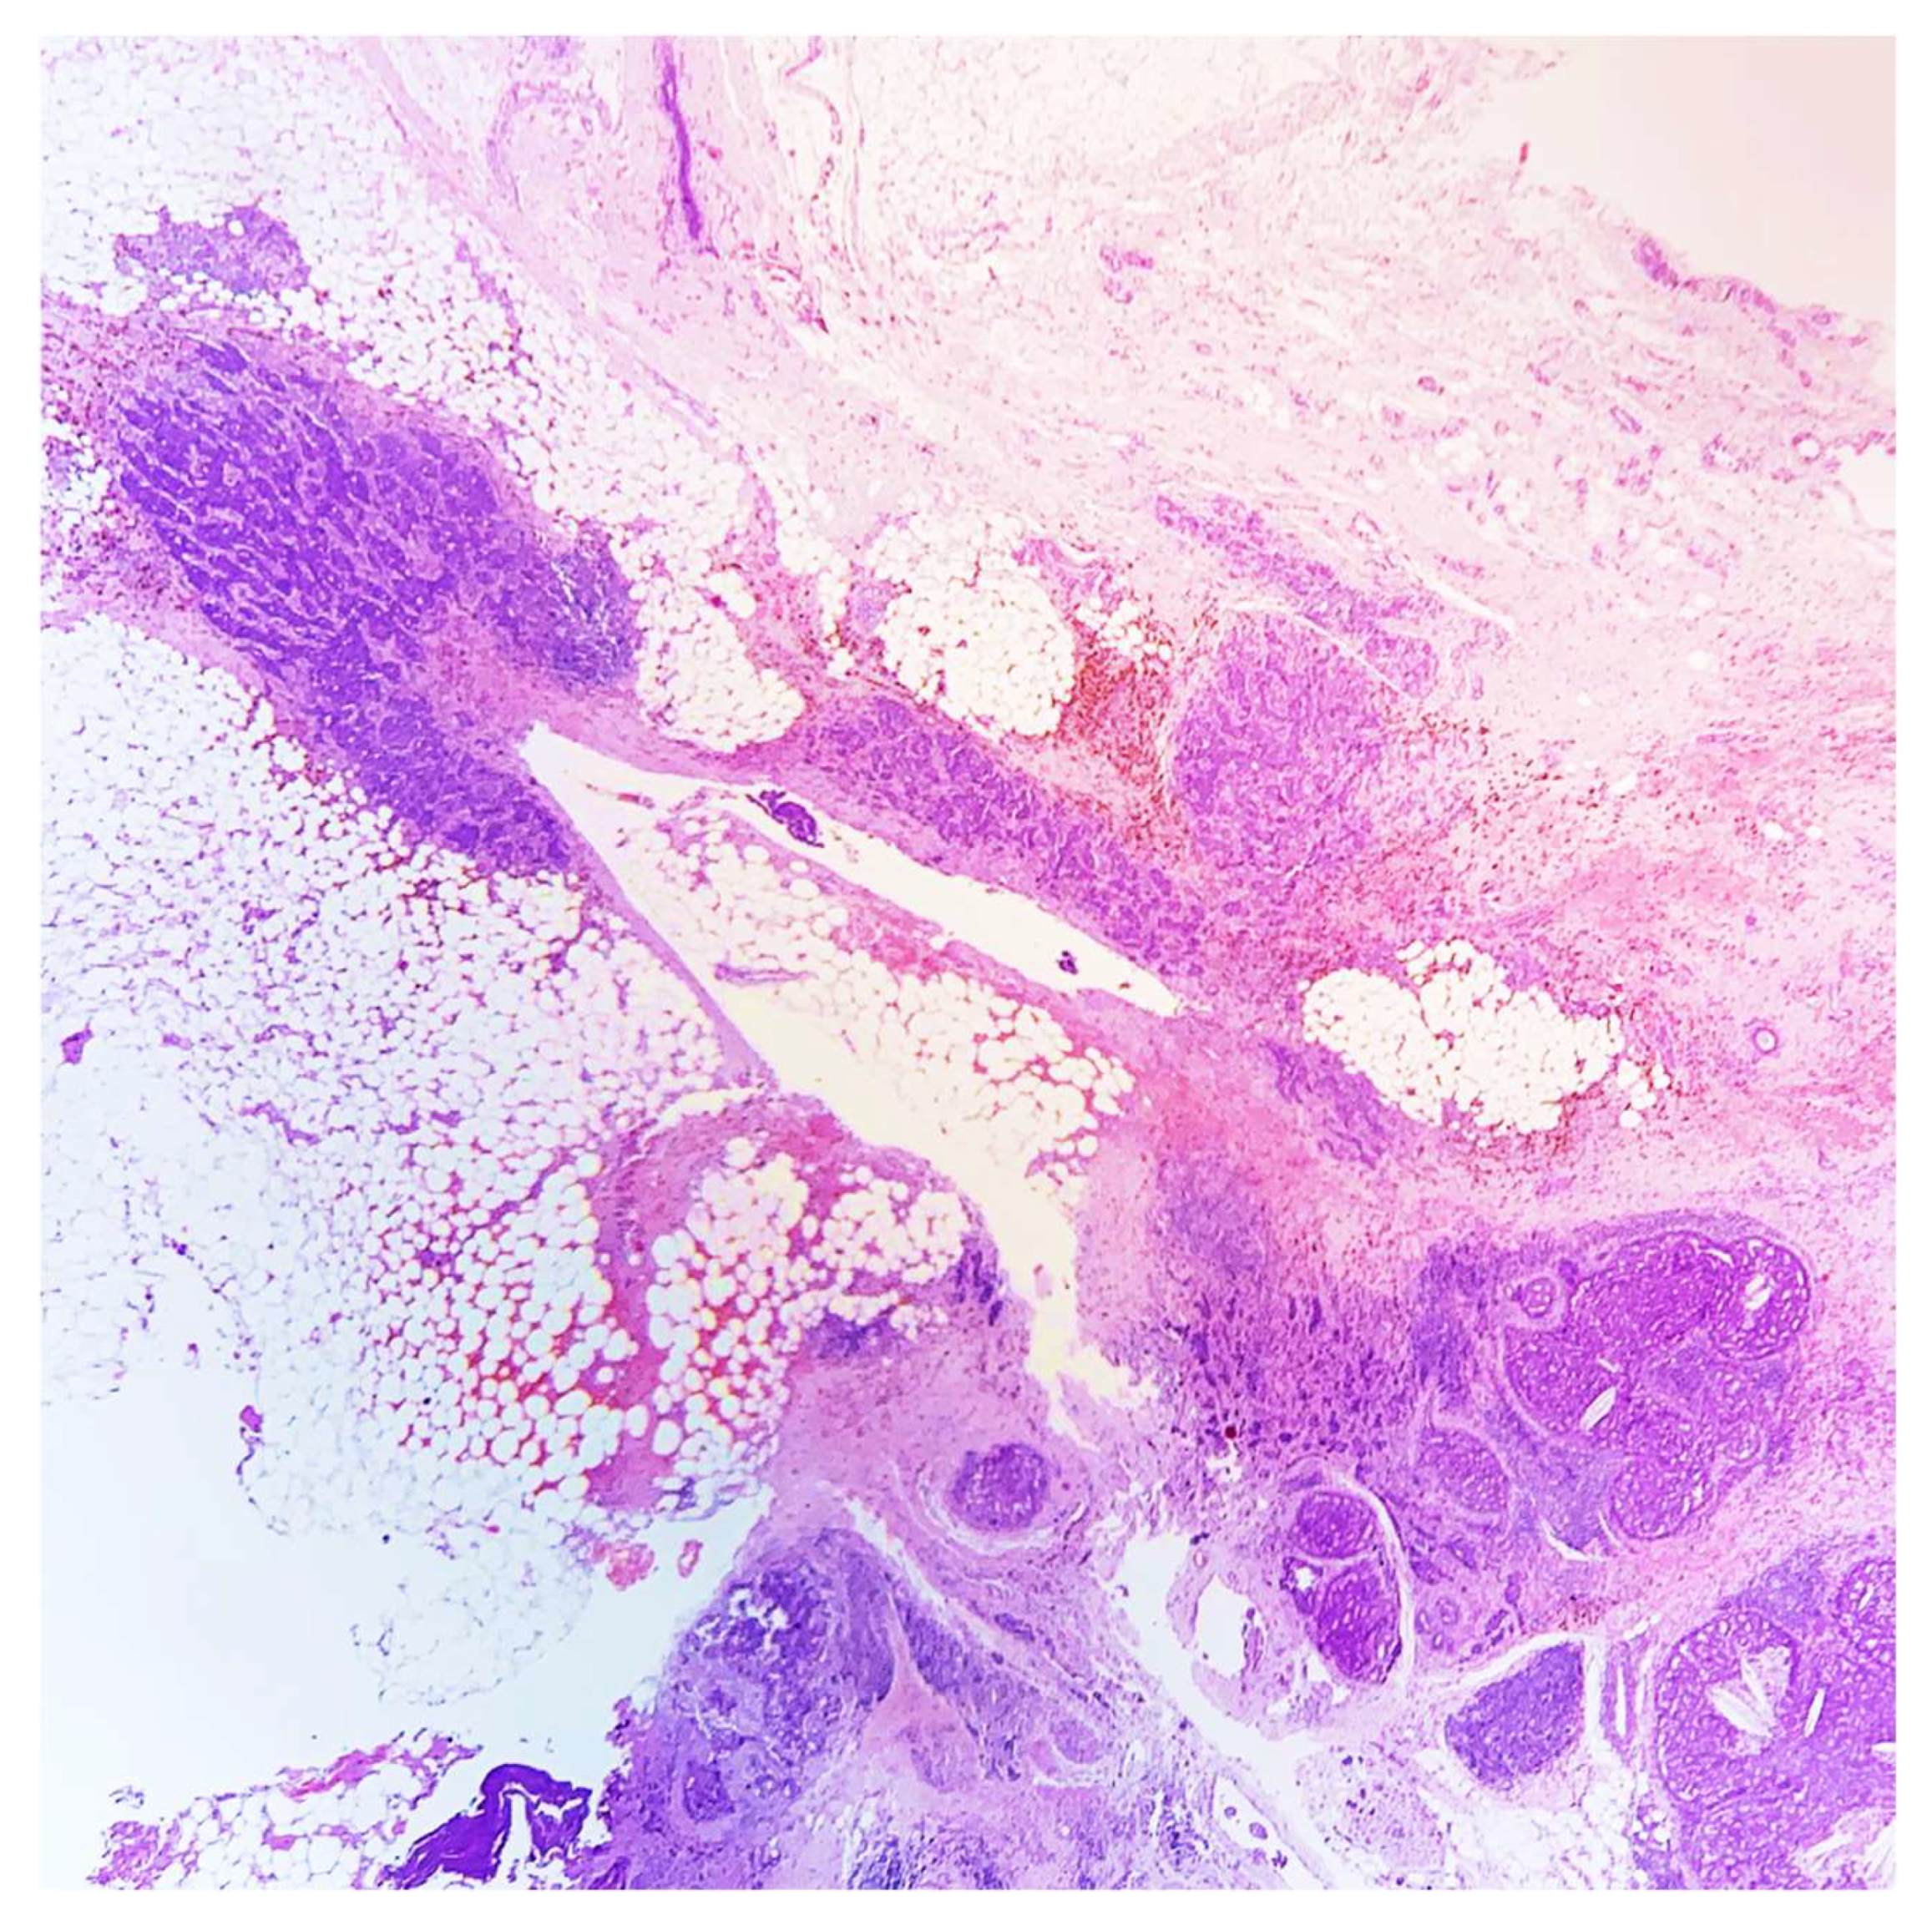

A 45-year-old lady, during her screening ultrasonography, was found to have an 8-millimeter solid mass in the upper outer quadrant of right breast, characterized by irregular margins and inhomogeneous internal echoes, suspicious for carcinoma. An ultrasound-guided core needle biopsy of the lesion was performed and a diagnosis of gland-forming breast carcinoma with many erythrocytes, hemosiderin, and stromal osteoclast-like giant cells was rendered. The neoplastic cells showed a moderate grade of atypia. No further assays were performed (Figure 1 and Figure 2).

Figure 2. Ultrasound-guided core needle biopsy showing invasive gland-forming carcinoma, associated with erythrocytes, hemosiderin, and many stromal osteoclast-like giant cells (HE, 200×).